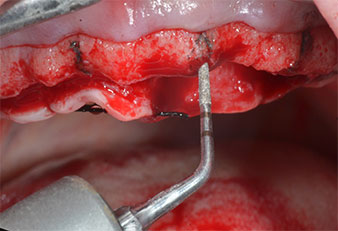

Un insert piézoélectrique diamanté de forme effilée (Piezomed I1) a été utilisé pour marquer les positions implantaires et effectuer la préparation pilote (Fig. 3). On a pris soin de travailler selon un mouvement ascendant et descendant, à puissance réduite, irrigation complète et basse pression (moins de 300g). Ensuite, un insert pilote (Piezomed I2A/I2P) a été utilisé pour l’agrandissement initial de 2mm du diamètre des sites implantaires (Fig. 4), suivi d’un insert de 3mm (Fig. 5).